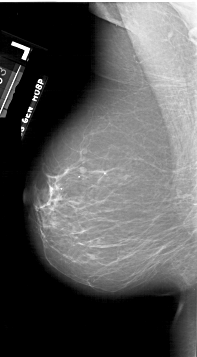

A_1747_1.LEFT_MLO

LEFT_MLO LINES 6421 PIXELS_PER_LINE 3541 BITS_PER_PIXEL 12 RESOLUTION 43.5 NON_OVERLAY